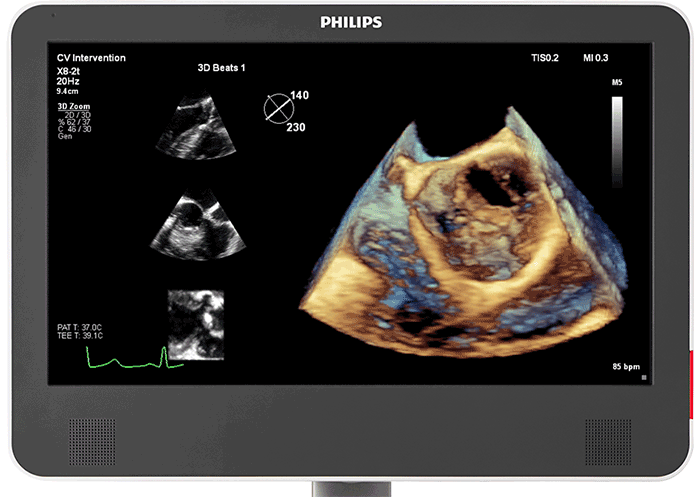

3D photorealistic rendering with virtual light source For improved visualisation of cardiac anatomy in the transthoracic and transesophageal echo, Philips cardiology TrueVue with its virtual light source makes it simpler to visualise the location of defects and comprehend depth within the structures. 90% of clinicians5 who saw the new Philips EPIQ CVx felt that the new TrueVue 3D photorealistic rendering provided improved viewing of anatomical structures, thus increasing clinical confidence.

Designed for next-generation Live 3D TEE The acoustic design of the Philips X8-2t Live 3D transesophageal transducer provides higher frequencies and bandwidth for increased resolution and tissue filling in 2D and Live 3D. It brings true one-beat acquisitions and our highest volume rates in Live 3D and Live 3D colour flow without compromise to image quality. Its handle is designed with a real-time configurable function button allowing for additional functionality while imaging.

Photorealistic rendering built for collaborative intervention suites For better visualisation of interventional devices, Philips cardiology TrueVue, with its virtual light source, is a proprietary and advanced 3D ultrasound display method. TrueVue makes it simpler to visualise the location of catheters and devices by providing images with tissue detail and depth perception. Since it offers a viewing context for the echo images, caregivers in the interventional suite can rely on support when communicating complicated echo images and enhance their procedural confidence. 90% of clinicians5 who saw the new Philips EPIQ CVx felt the new TrueVue 3D photorealistic rendering improved viewing of anatomical structures thus increasing clinical confidence2.